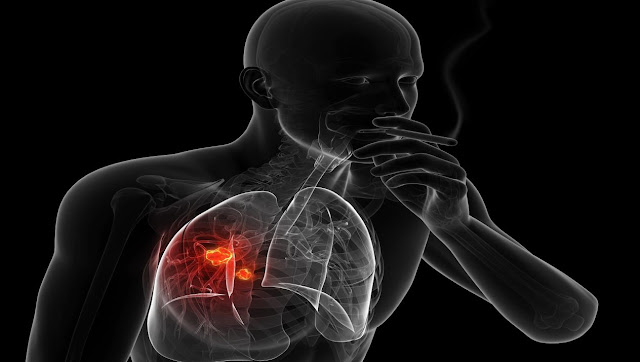

- التدخين: خطر الإصابة بسرطان الرئة يزداد مع زيادة عدد السجائر اليومية وعدد السنوات بالنسبة للمدخن.

أعراض سرطان الرئة

- سعال يدوم أكثر من بضعة أسابيع.

- سعال الدم.

- الصفير في التنفس.

- آلام الصدر.

- آلام عند التنفس أو السعال.

- ضيق التنفس.

- بحة في الصوت.